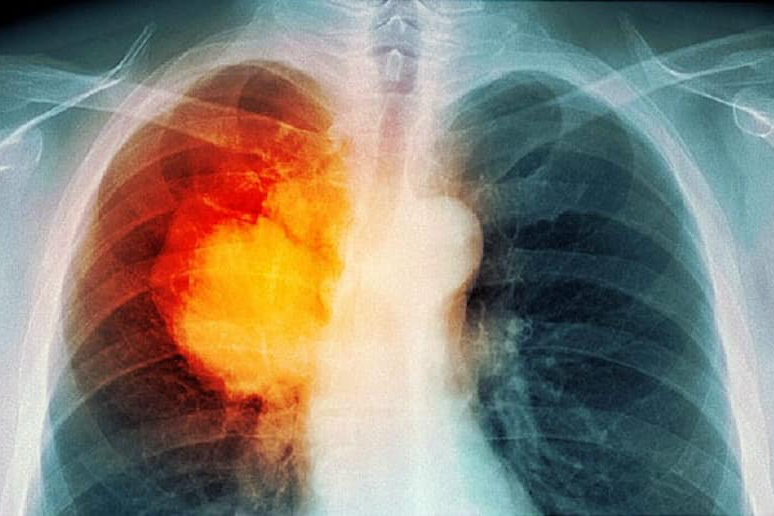

Ung thư phổi là căn bệnh nguy hiểm và chỉ 14,8% số bệnh nhân sống qua 5 năm, giải pháp quan trọng là sàng lọc bằng chụp CT liều thấp để phát hiện sớm.

Việt Nam có hơn 26.000 ca mắc mới và 23.000 ca tử vong vì ung thư phổi. Nhiều phương pháp tầm soát căn bệnh ác tính này được giới thiệu, trong đó có xét nghiệm máu tìm chỉ số ung thư.